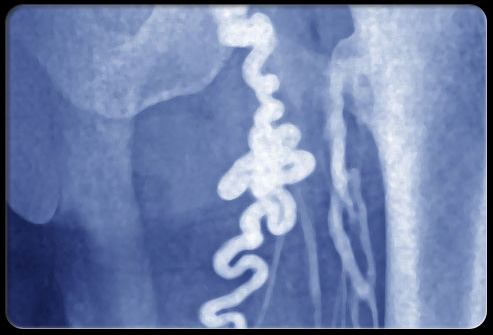

盆腔淤血综合征

盆腔疼痛怎么引起的,盆腔疼痛是什么原因引起的

盆腔淤血综合征是血流速度慢导致的盆腔静脉肿胀疼痛,和腿上的静脉曲张一样。这种盆腔疼痛通常会随着*坐静**或站立而加重,平躺则可能缓解症状。治疗方法可能涉及药物或接入栓塞(组织血流进入受影响的静脉)。